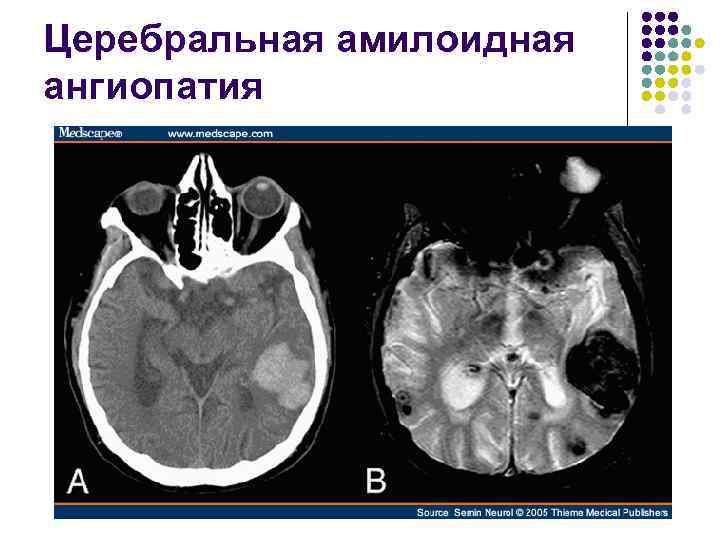

Церебральная амилоидная ангиопатия l l Отложение β-амилоида в медии и адвентиции мелких и средних артериях мозга Рецидивирующие преимущественно лобарные кровоизлияния

Церебральная амилоидная ангиопатия